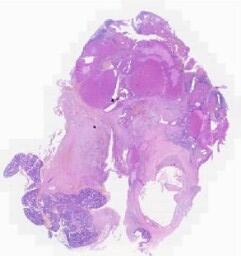

临床资料: 患者,女性,53岁,因“绝经5年,检查发现盆腔占位2年”入院。患者2年前外院体检,彩超发现盆腔内囊性占位,约2.8cm,平素无下腹疼痛,无阴道流血,院外未治疗。入院前11天,患者无明显诱因出现尿频、尿急,无尿痛、血尿等,于我院泌尿外科就诊,行泌尿系统及腹部彩超检查发现右肾结石、右肾囊肿,盆腔内查见10.3×8.1cm囊状无回声区,考虑卵巢肿瘤?予以口服药物治疗后尿频、尿急症状明显缓解,为进一步治疗盆腔囊肿,故入院。查体:外院已婚已产型,阴道通畅、壁光滑,宫颈光滑,大小形态正常,无举痛及摇摆痛,子宫呈前位,边界清楚,正常大小,质中,活动,无压痛,盆腔偏右侧触及一直径约10cm的囊性包块,边界清楚,活动,无压痛,双附件未触满意触及。辅助检查:彩超示盆腔内查见大小约10.2×8.1cm的囊状无回声区,边界清晰,形态规则,其内未见血流信号。磁共振示盆腔可见一椭圆形长T1长T2信号脂肪抑制序列为高信号,DWI呈稍高信号,大小约86mm*108mm*93mm,边界清晰,子宫受压轻度后移,增强后囊内未见异常强化征象,囊壁环状强化。

大体所见: 大体检查:送检(右侧附件)灰白色已剖囊性包块一个,体积6.0×4.5×1.5cm,表面附着输卵管一条,长6.0cm,直径0.3-0.5cm。

免疫组化: 无